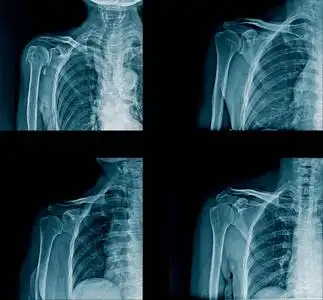

骨肌左肩关节病变请会诊

昨晚我意外摔倒,左手冲击性着地,左肩肩膀疼痛不已,不能活动.

摔伤左肩部疼痛l小时

男性50岁左肩是骨折吗

男,请根据其正常肩关节影像图像,判断其最可能的年龄()